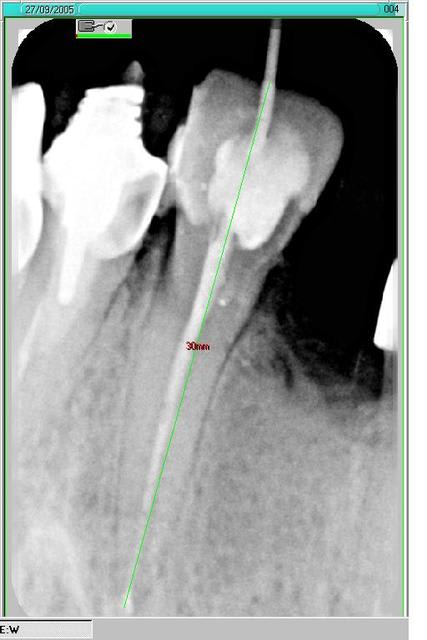

Petit alésage manuel lime 21 jusqu'a la garde, radio lime en place. Et bé, mon gars tu peux prendre une 25. Pareil , qu'il est loin mon apex adoré. Bon bé pas de foin, une lime 28 et radio a l'archigarde. Bon bé c'est presque bon.

Petite mesure avec les ragnagnas , euh je veux dire le réglet de julie: 30mm, la 21, balèze , hein?

Ci joint la radio post op. Je fais concurrence a mon ami athos (sans atteindre sa perfection en endo, snif) dans l'art véto!